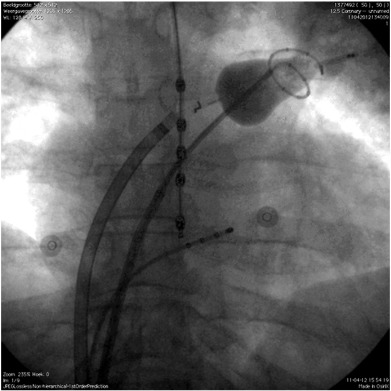

Fluoroscopic image of the setup of the endoscopic laser balloon system (PA ...

Fig. 1.

Fluoroscopic image of the setup of the endoscopic laser balloon system (PA view).

The CMC was inserted transseptally into the left atrium and placed in the left superior pulmonary vein (LSPV). The laser balloon catheter was also inserted transseptally into the left atrium and positioned in the LSPV proximal to the CMC. The temperature probe was positioned in the oesophagus. The quadripolar catheter was positioned in the coronary sinus.